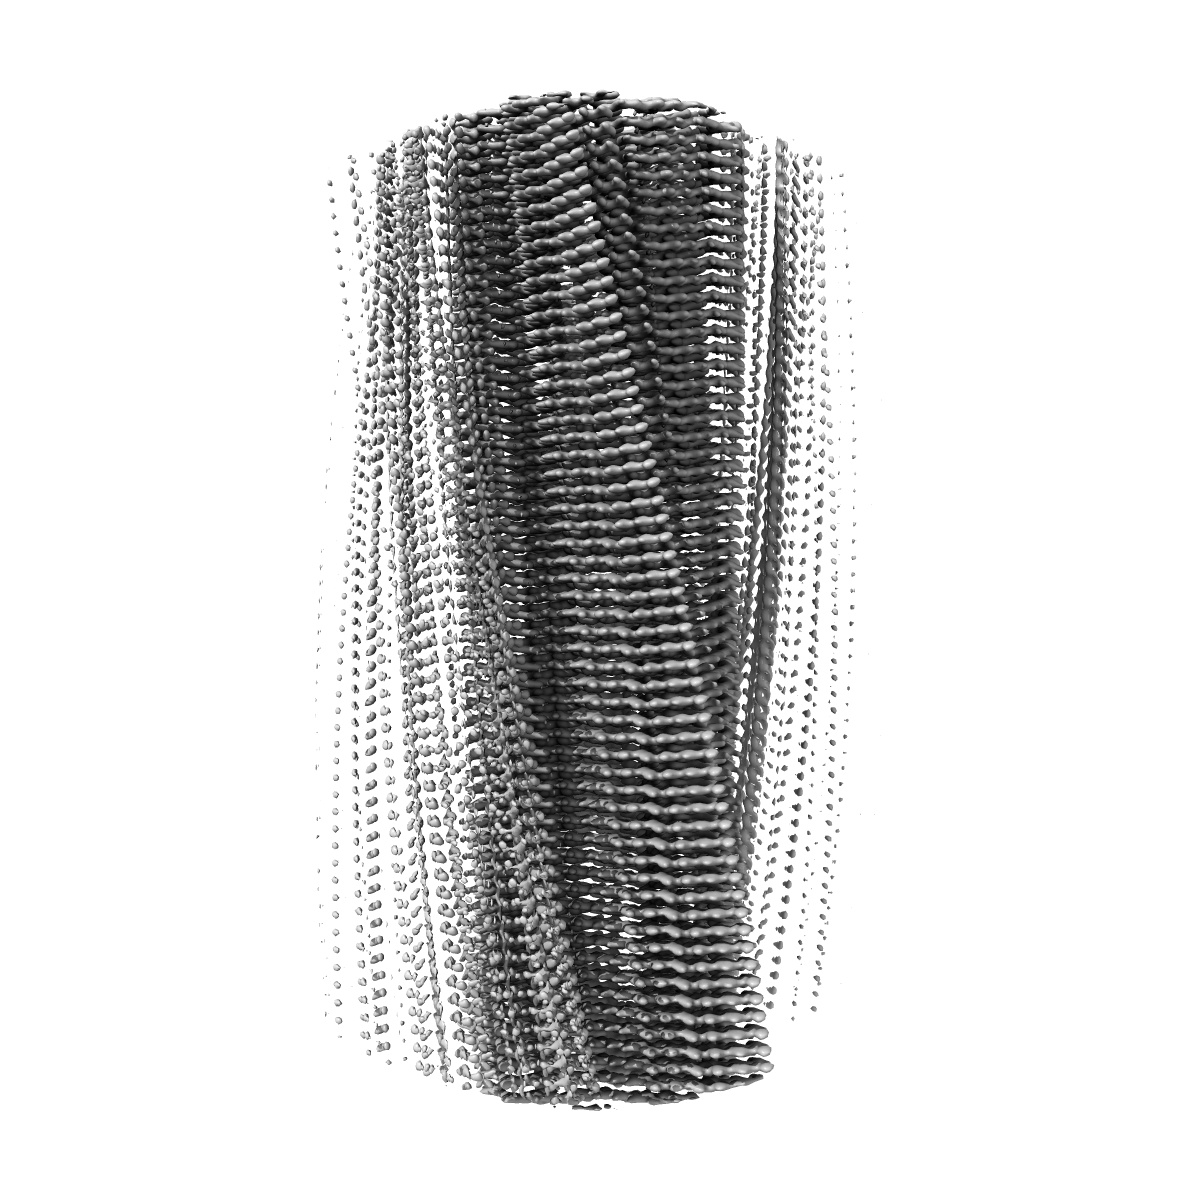

In vitro assembled 266/297 - 391 tau filaments with MgCl2 and NaCl (14b)

Assembly of recombinant tau into filaments identical to those of Alzheimer's disease and chronic traumatic encephalopathy.

Lovestam S, Koh FA, van Knippenberg B , Kotecha A , Murzin AG, Goedert M , Scheres SHW

(2022) eLife , 11